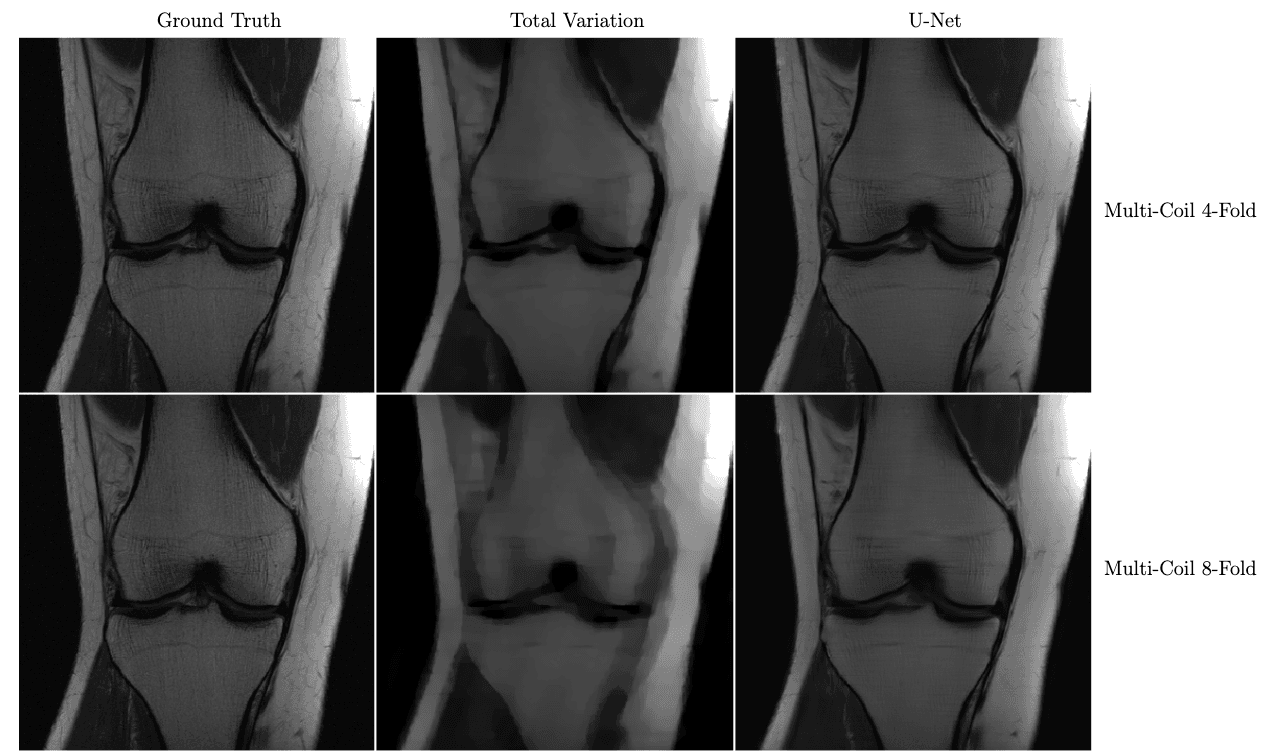

In the figure below, we see a significant qualitative improvement in the reconstructions from the U-Net, in comparison with traditional compressed sensing with total variation regularization.

Knee MRI reconstructions comparison between compressed sensing with total variation regularization and the fastMRI U-Net baseline.

The data is acquired using multiple coils at 4x and 8x subsampling. Reproduced from Zbontar et al. 2018.